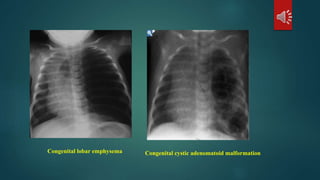

Congenital:

congenital lobar emphysema

congenital adenomatoid cyctic malformation of a lobe.

Congenital cystic adenomatoid malformationCongenital lobar emphysema